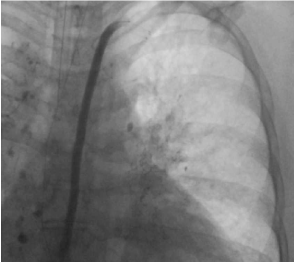

In view of these findings, a magnetic resonance (MR) lymphangiogram was performed showing abnormal pulmonary lymphatic perfusion with communication between retroperitoneum and pleural spaces, for which she needed a post thoracic duct stenting to improve lymphatic outflow and prevent left side leak (Figure 8). Then underwent embolization of right-side thoracic duct leak that was communicating with the right pleural cavity, however, due to an identified persistent leak on MR lymphangiogram, conventional thoracic duct embolization was once again implemented, this time to the mid-mediastinum central thoracic duct abnormality (Figure 9 and10). Results yielded remarkable improvement in condition and no post-procedure complications. Our patient is currently on follow up at our pulmonary clinics in stable condition and has remained asymptomatic.

Figure 9. Thoracic lymphangiography with stenting of the central and distal portion of the thoracic duct